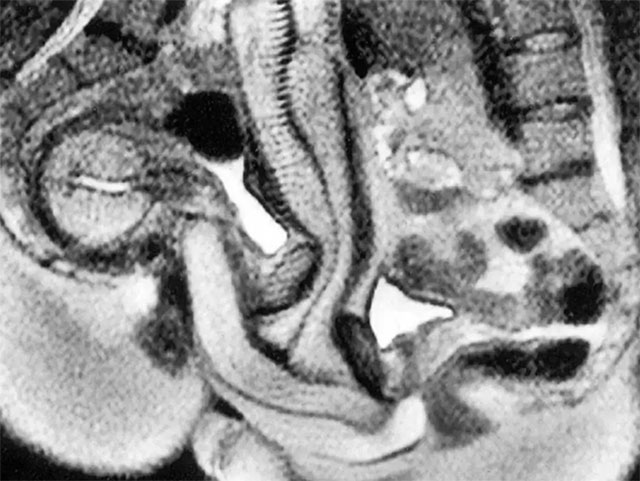

Ein Paar hatte Sex in einem MRT-Gerät, um herauszufinden, was während des Geschlechtsverkehrs im Körper passiert

Wenn Sie Ihre Beziehung im Jahr 2026 aufpeppen möchten, reicht es vielleicht nicht, einfach nur im Kama Sutra zu blättern. Manche Paare, die Neues ausprobieren wollen, möchten vielleicht abenteuerlustiger werden und ihr Liebesleben aus dem Schlafzimmer an neue Orte verlegen (im wahrsten Sinne des Wortes). Wir möchten darauf hinweisen, dass wir keine Verantwortung übernehmen können,…